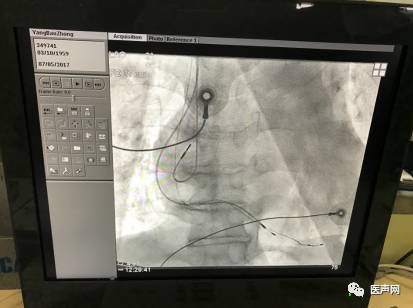

本例患者药物治疗9年无效,LVEF〈 26%,左室壁整体运动减低,全心增大室性早搏,左束支阻滞形,QRS〉136MS左室扩大。动态心电图(2017-6-26)显示窦性心律,房性心律失常总心博数为128次占心率的0.111%,室性心律失常总心搏数为5431次,占总心率的4.689%。患者左侧锁骨下造影发现患者为永存左上腔,左锁骨下静脉汇入冠状经脉窦,并与右侧锁骨下静脉无交通分支,右侧外周静脉周围血管造影,患者右锁骨下静脉经右上腔静脉汇入右房。决定经右侧植入CRT进行心脏再同步化治疗,最终顺利完成手术。

心脏彩超提示,左室壁整体运动减低、全心增大、主动脉窦部稍微增宽、肺动脉稍微增宽、二尖瓣中量反流、主动脉瓣少量偏多反流、三尖瓣少量反流,左心室收缩功能低下(LVEF〈 26% )。12导联心电图显示窦性心动过速、室性早搏、左束支阻滞形、QRS〉136MS,R波上升不良;ST段异常,未见明显T波改变。BNP:1286ng/L。患者左侧锁骨下造影发现患者为永存左上腔,左锁骨下静脉汇入冠状经脉窦,并与右侧锁骨下静脉无交通分支,右侧外周静脉周围血管造影,患者右锁骨下静脉经右上腔静脉汇入右心房。

该患者心力衰竭反复发作长达9年,患者左侧锁骨下造影发现患者为永存左上腔,左锁骨下静脉汇入冠状经脉窦,并与右侧锁骨下静脉无交通分支,右侧外周静脉周围血管造影,患者右锁骨下静脉经右上腔静脉汇入右心房。,经静脉植入左室电极难度较大,手术风险极高。

通过左室递送系统鞘管6250MPR在右侧经静脉放置起搏右房、右室、左室导线,囊袋制作。

造影图片: